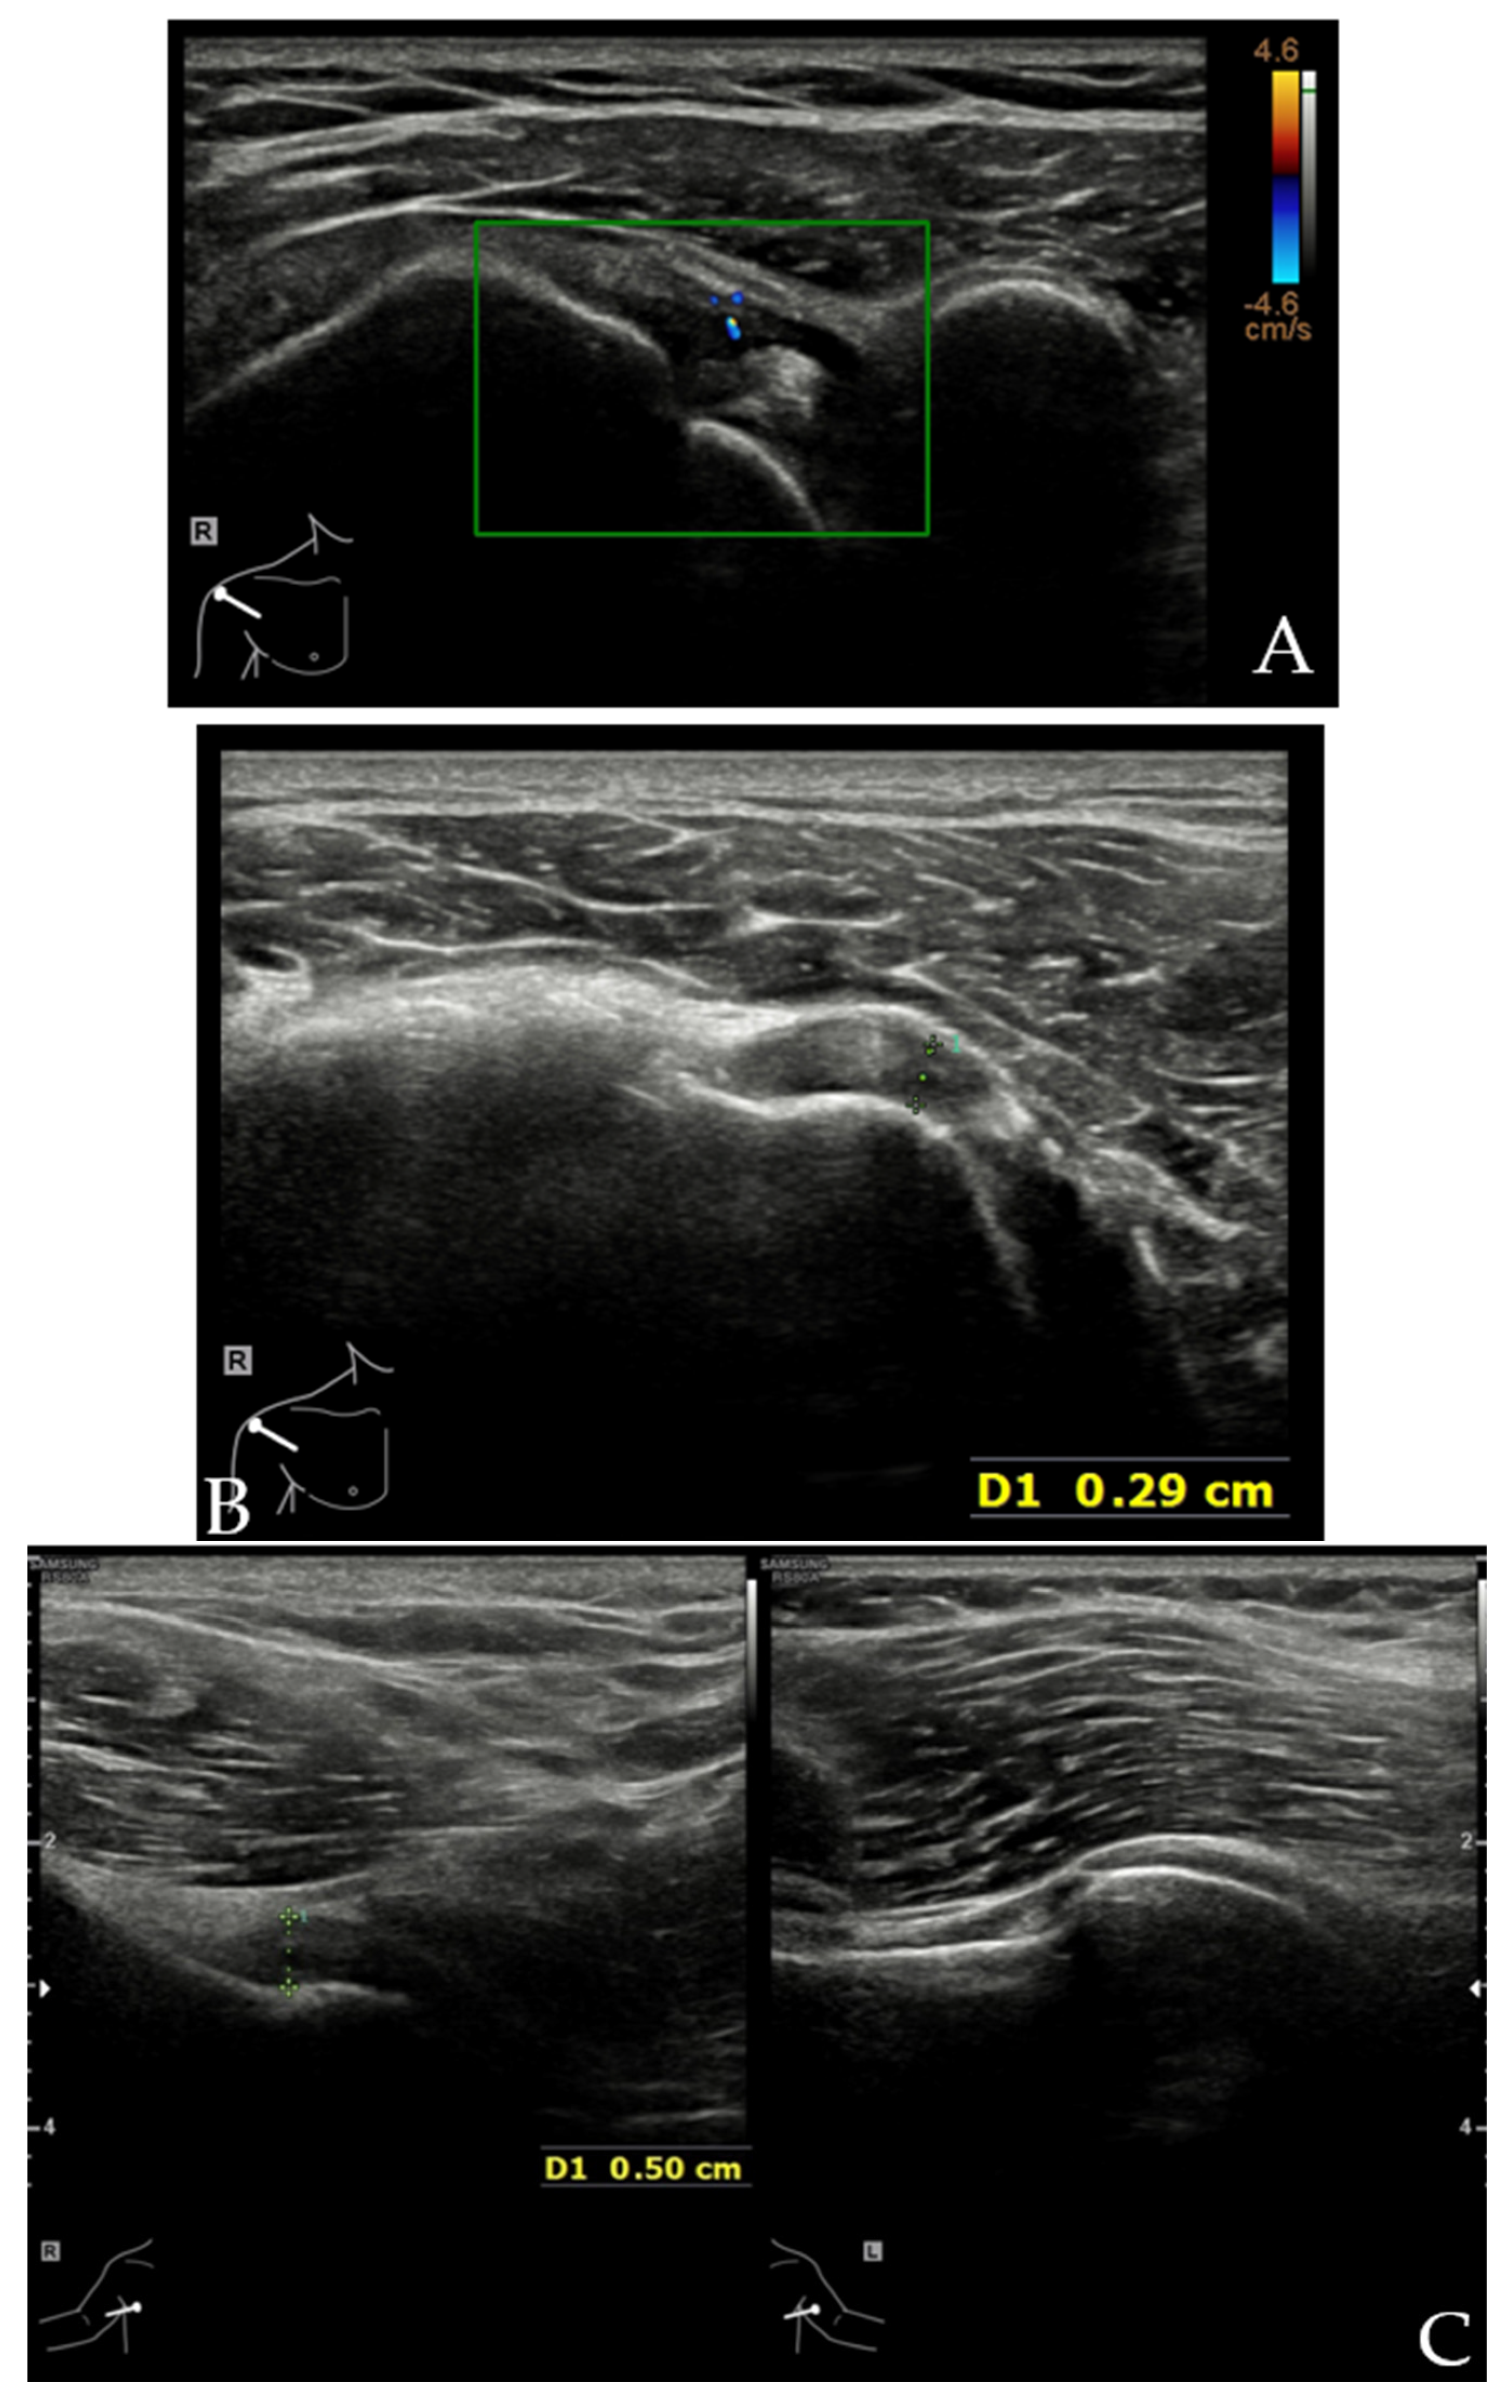

4.4. PM Tendon Tears

4.5. Injuries to the LD and TM